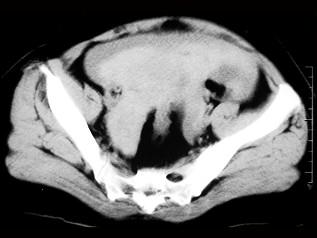

问题 女 ,32岁 ,因停经46天 ,少许不规则阴道流血15天 ,下腹胀痛 3 天入院,后穹窿穿剌抽出不凝血,CT检查如图所示,下列说法错误的是 ( )

选项 A、此为宫外孕 B、此为卵巢巧克力囊肿 C、病灶外缘较光整 D、盆腔内较高密度积液 E、在左附件区可见一椭圆形略高密度病灶

答案 B